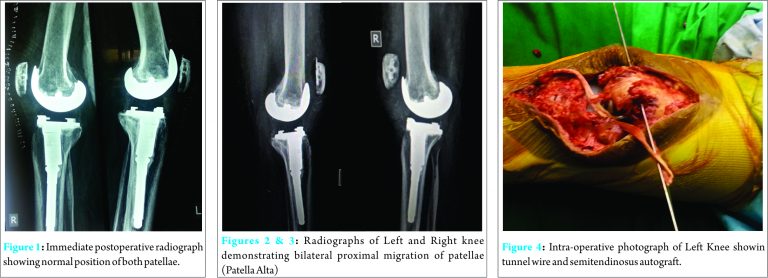

A 69-year-old male underwent bilateral sequential knee arthroplasty with patellar resurfacing for grade 4 osteoarthritis with bilateral fixed flexion feformity of 30-40 degrees. He was also diabetic and had cardiac ejection fraction of only 20%. Surgery was uneventful with good post-operative recovery. He had normal patellar position on post operative radiographs (Fig. 1). Post TKA, rehabilitation protocols were initiated and he was able to achieve limited indoor ambulation within three days. He continued with range of motion and strengthening exercises along with proprioceptive training. Surgical drains were removed on the 2nd post-operative day and he was discharged on 7th post-operative day. By this time, his range of motion (ROM) was more than 90 degrees and muscle strength in quadriceps was MRC grade 4/5. On 30th post operative day, he experienced buckling and excruciating pain in both knees while getting up from a low lying toilet chair and he was unable to stand. He could not extend his knees, which were swollen. He required assistance from family member for mobility. After that incident, he was unable to walk without support due to severe pain and the knees giving way on weight bearing. He sought medical advice after 2 days when the pain and swelling did not improve. On enquiry, there was history of three intraarticular steroid injections within a period of one-year. This was two years before the patient presented to us for knee arthroplasty. Upon examination, both knee joint were warm, tender and swollen. Swelling and skin discolouration were suggestive of hematoma formation. He was unable to actively extend his knee joint and the range of motion was painful. The patella was mobile and high riding on clinical examination. X-ray of the knee joint revealed patella alta (Fig. 2 and Fig. 3) while rest of the joint was normal. MRI of the both knee was done and it revealed bilateral patella midsubstance tendon rupture. Bilateral patellar tendons were repaired with augmentation by semitendinosus graft and anchors over tibial tuberosity (Fig. 4-6 ).